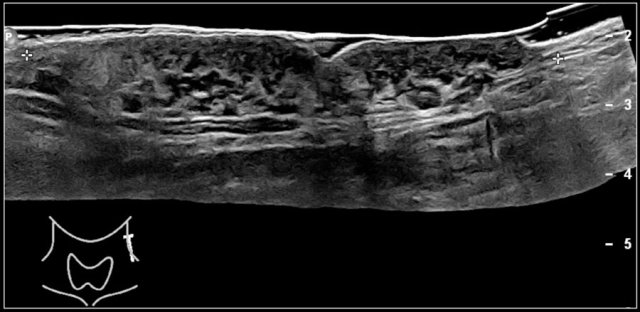

Here an image of a 16-year-old girl with hyperthreoidism.

A diffusely enlarged thyroid gland is seen with hyperemia.

The final diagnosis was Graves disease.

She was treated with I-131.